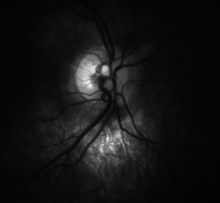

![High detail picture of optic disc [epiCam].](../I/m/Optic_disc_detail.png)

Traditional colour-film camera images are the reference standard in imaging, requiring an expert ophthalmic photographer, ophthalmic technician, optometrist or an ophthalmologist for taking standardised pictures of the optic disc. Stereoscopic images offer an excellent investigative tool for serial follow-up of suspected changes in the hands of an expert optometrist or ophthalmologist. In recent times high resolution real-time video of the optic disc has allowed for the analysis of blood-flow and vasodilation in vessels in the area of the disc (epiCam) which may help to quantify both retinal and systemic disease.

Automated techniques have also been developed to allow for more efficient and less expensive imaging. Heidelberg Retinal Tomography (HRT-II), GDx-VCC and optical coherence tomography (Stratus-OCT 3) are the currently available computerised techniques for imaging various structures of the eyes, including the optic disc. They quantify the nerve fiber layer of disc and surrounding retina and statistically correlate the findings with a database of previously screened population of normals. They are useful for baseline and serial follow-up to monitor minute changes in optic disc morphology. Imaging will not provide conclusive evidence for clinical diagnosis however, and the evidence needs to be supplanted by serial physiological testing for functional changes. Such tests may include visual field charting and final clinical interpretation of the complete eye examination by an eye care physician. Ophthalmologists and optometrists are able to provide this service.